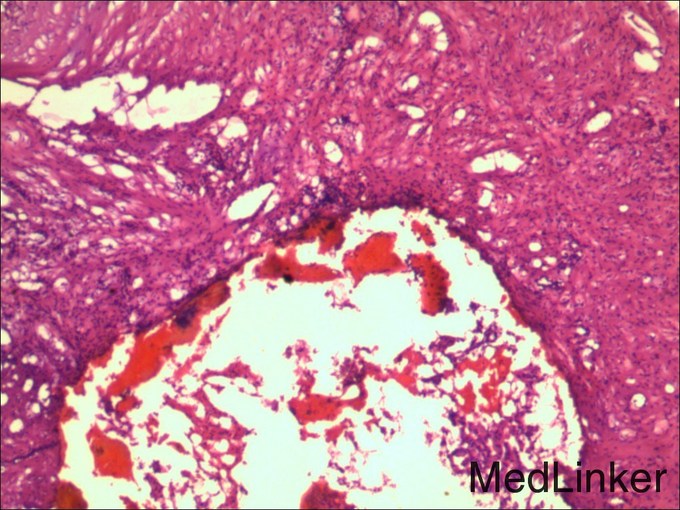

临床诊断 肝细胞癌 治疗: 手术切除右侧肾上腺转移瘤和右肝肿瘤 术后病理: 1、(肝)送检4x3x2cm灰褐色组织一块,切面灰黄,质软。 镜下:送检肝组织内见境界较清楚的胶原纤维包裹的坏死结节,其内可见肿瘤残影,建议结合临床患者是否行介入等治疗,则可符合治疗后改变,未见残留肿瘤细胞。另一组织提示增生的肝细胞Glypican-3灶性(+),CD34显示增生的结节毛细血管化。 特殊染色:网状纤维染色显示肝细胞索增生。 结合HE形态及免疫组化结果,病变符合肝细胞癌。 2(肾上腺结节)送检5x3x3cm淡黄组织一块,可见直径2cm灰白结节。 镜下:肾上腺组织内见肝细胞癌浸润。